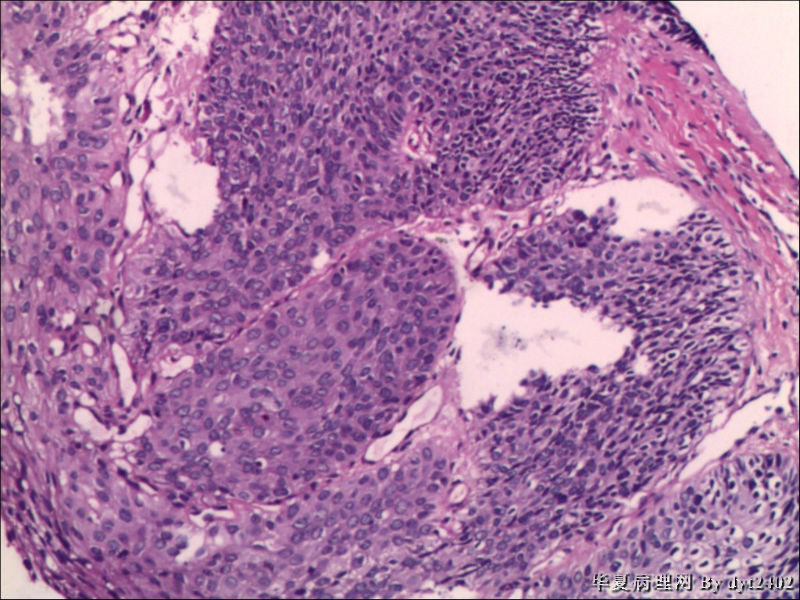

这样的外阴病变 发个原位癌是否合适?

图2

VIN III,做个银染或者标个免疫组化看一下基底膜是否完整。

看上去好像还完整 只是经常看见图5 那样结构的就觉得可能还有更重病变